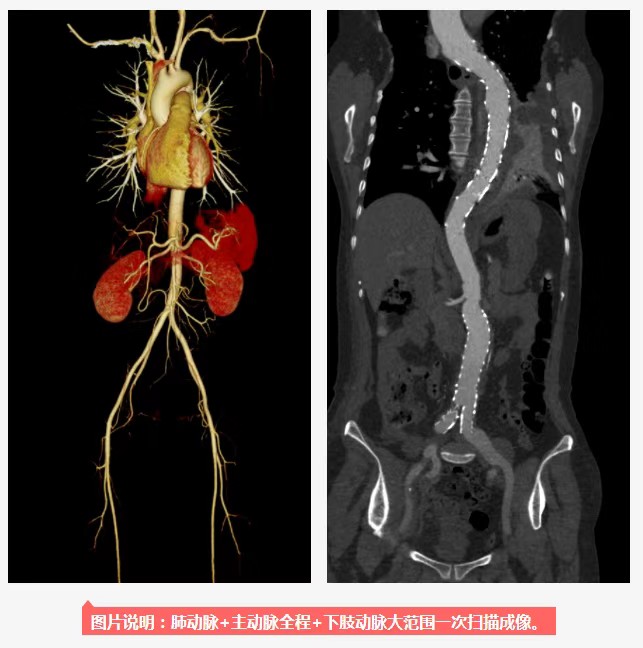

大范围低剂量CTA成像

采用业内最先进液态金属轴承技术的超大热容量球管,结合独有的低千伏、低毫安成像模式,天河640可实现冠脉、主动脉、下肢动脉等全身各部位大范围扫描、微辐射剂量的检查。低千伏扫描模式有效降低辐射剂量、对比剂总量、对比剂浓度、对比剂注射速率,降低肾功能不全受检者增强检查风险、减少对比剂外渗风险、并可大幅度提升增强检查碘对比剂对比度,提升强化效果;同时,系统还可根据不同患者体型和扫描协议自动推荐扫描管电压,在降低患者扫描剂量的同时,优化对比度噪声比。(刘珊珊)